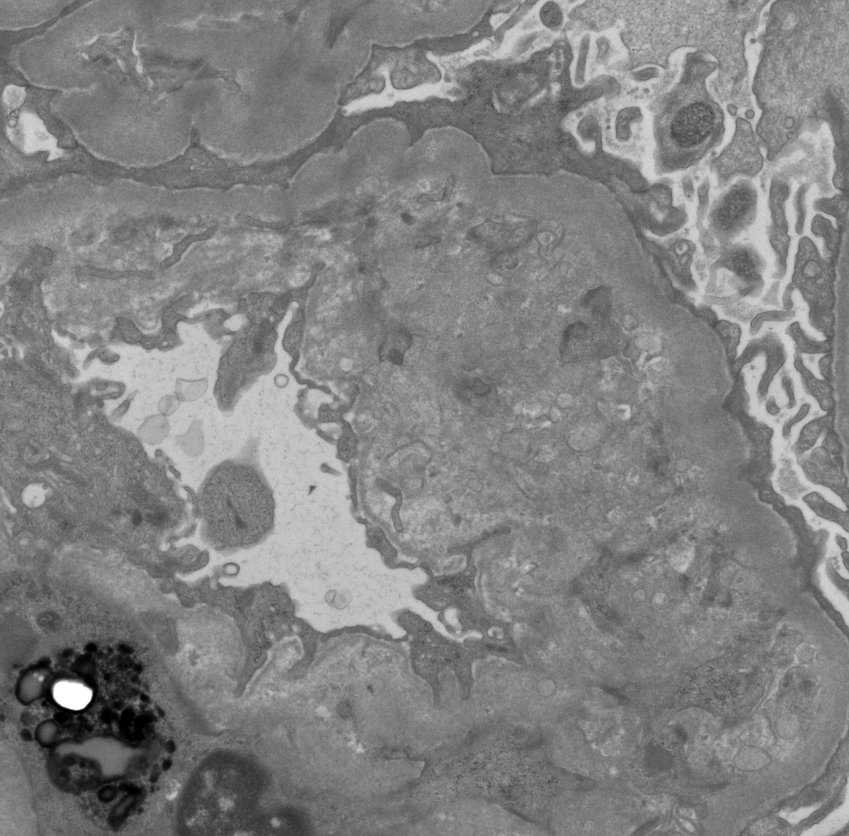

A startling biopsy. Severe acute TMA in a pt with suspected scleroderma renal crisis. Massive vascular thrombosis, mucoid intimal edema, and early onion skin change associated with severe cortical necrosis. #renalpath #nephrology #pathtwitter

3

30

72